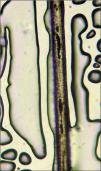

El examen con microscopia de luz óptica de un fragmento de pelo mostró cúmulos pigmentarios, de forma y tamaños irregulares, distribuidos de manera uniforme (fig. 2). Este dato nos abrió la sospecha de los síndromes de Griscelli, Chediak-Higashi y Elejalde.